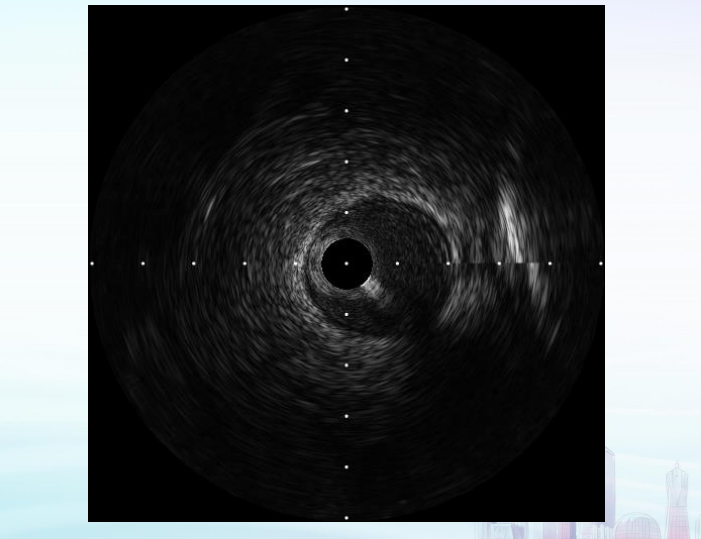

董鹏教授分享的临床图像均体现出超宽频技术优秀的分辨力,洞悉纤细结构的同时能够保证充足的穿透深度。相比于传统陶瓷IVUS,开立超宽频IVUS系统能够高清反映血管壁结构、斑块形态及支架植入情况,具有高清分辨力,成像深度更充足。

虞旭东教授展示了一例IVUS指导下的CTO病变处理。冠脉造影提示前降支中远段CTO,IVUS检查确认导丝位于血管真腔,前降支中远段弥漫病变。球囊扩张后,残余狭窄90%,遂于病变位置植入2.75*40、3.0*30支架各1枚,后复查IVUS显示支架扩张充分,贴壁良好。

陈海波教授带来一例IVUS指导完成的分叉病变。冠脉造影提示三支病变,造影提示右冠原支架通畅,血管未见明显狭窄,左主干末端分叉病变,前降支、回旋支开口重度狭窄伴钙化。经球囊预扩后分别对LAD、LCX行IVUS检查,结果提示回旋支弥漫病变,近端超过270°重度钙化,前降支远端肌桥,近端180°钙化。术后复查IVUS显示支架膨胀充分,贴壁良好。

陈翔教授分享了一例IVUS指导完成的前降支PCI病例。冠状动脉CTA提示前降支近端重度狭窄。球囊预扩张后IVUS检查提示:前降支近端重度狭窄,病变延伸至前降支、回旋支、中间支三分叉处。支架后IVUS查看显示支架贴壁不良,球囊后扩,复查IVUS显示定位准确,未影响中间支和回旋支开口。

在大会PCI手术直播中,广东省人民医院张斌教授、浙江大学医学院附属第二医院朱玲军教授、浙江医院金红峰教授的PCI手术演示中,开立超宽频IVUS术中清晰的影像支持和充足和穿透深度,也为成功完成手术提供了强大的助力,实现了精准优化的PCI治疗效果。